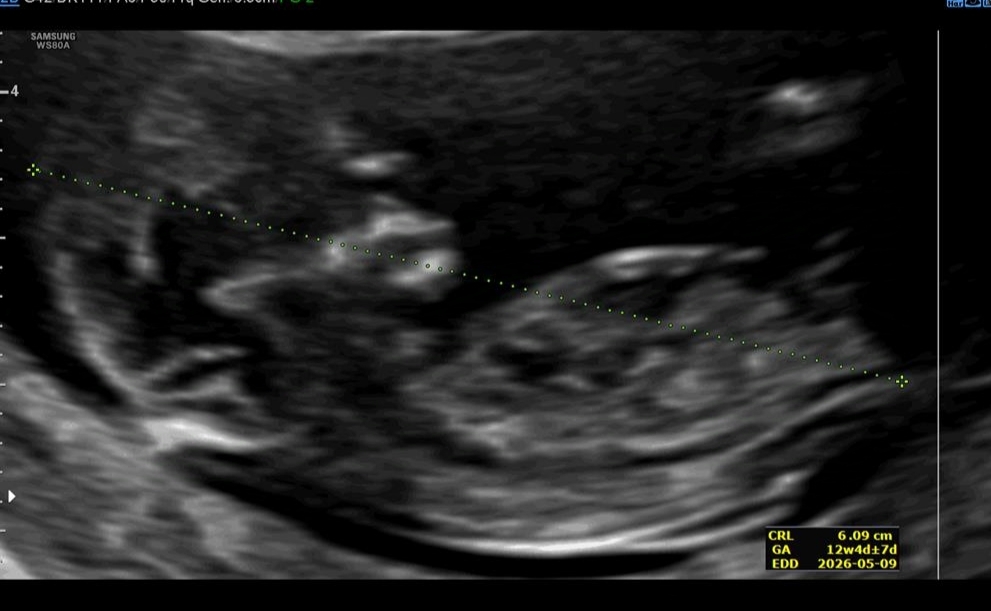

ان تی و جنسیت عکس

تو ان تی دکتر جنسیت و بهتون گفت ؟! چند درصد درست بود ؟ به من گفت احتمالی میگم دختر ولی اصلا مشخص نیست

به من گفت ۸۰ درصد دختره اونم با نگاه به نیمرخش و اینا نمیدونم چقدر درسته